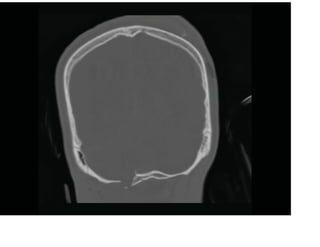

Fenêtres osseuses avec balle logée

Les images tomodensitométriques

axiales des diapositives suivantes

montrent le point d'entrée de la balle

dans le crâne occipital droit avec des

fragments de fracture comminutive.

Les données du scanner peuvent

être reformatées dans le plan

coronal pour évaluer les fractures

du calvaire.